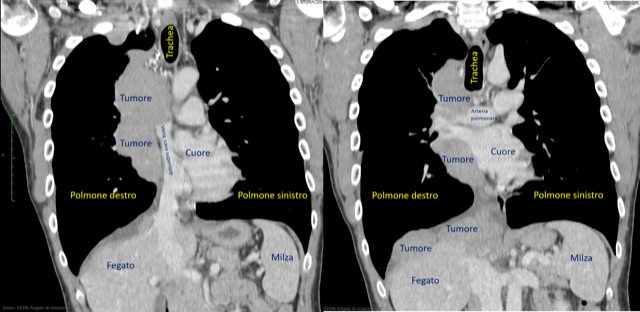

Eccezionale intervento di chirurgia toracica all’ospedale Borgo Trento di Verona: a un giovane paziente è stato asportato un enorme tumore (timoma) che gli aveva invaso il torace e il polmone destro, occludendo la grande vena cava superiore e colonizzato con metastasi l’interno della parete toracica e la superficie del diaframma.

L’uomo è stato operato con successo dall’équipe della Chirurgia toracica composta dal direttore Maurizio Infante, e da Riccardo Giovannetti, Alessio Campisi e Maria Carlotta Marino. L’intervento col quale i chirurghi hanno completamente rimosso la massa ha richiesto sofisticate metodiche di risonanza magnetica cardiaca per accertare la possibilità di asportare completamente il tumore.